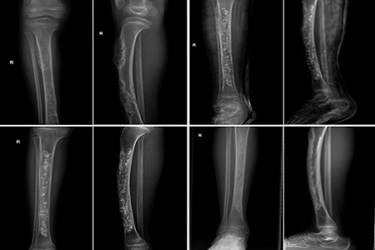

In a preliminary clinical study, 16 patients (11 male and five female) with a range of four different bone defects were surgically implanted with CHACC. Results showed there was clinical bone healing four months after surgery and the majority of the implanted CHACC degraded after 18 to 24 months in each patient.

The results of the small clinical study, which have been published today, 29 November 2013, in IOP Publishing’s journal Biomedical Materials, showed that bone healing was observed in each of the patients after four months and that the CHACC had fully biodegraded after two years.